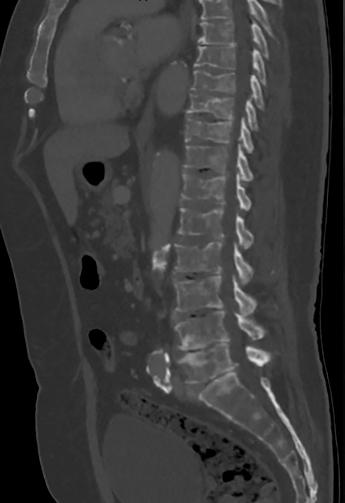

HNE: Roði í slímhimnu (conjunctiva) og hvítu (sclera) sem náði ekki að glærubrún (mynd 1A). Þroti í kringum augu en enginn gröftur. Ekki hor í nösum eða roði í hálsi en lítil blaðra á innanverðri kinn hægra megin. Varir þrútnar, rauðar, þurrar og sprungnar (mynd 1B).Hvít skán á bólginni tungu (mynd 1C).Eitlastækkanir beggja vegna á hálsi. Hjarta og lungu:Hjartahlustun eðlileg.Radialis púlsar sterkir og reglulegir. Lungnahlustun hrein.Góð háræðafylling.  Kviður: Mjúkur og eymslalaus. Húð: Mikið af rauðum blettóttum útbrotum ílófumogáiljumþarsemþauvorueinnigorðin samfelld (confluent) (mynd 1D). Hringlaga og markskífulaga (targetoid) ljósrauð blettótt útbrot á bringu, baki, fótleggjum og kvið og í holhönd og nára. Mismunandi að stærð frá nokkrum mm uppí 2-3 cm.

Mynd 1. Einkenni við komu á bráðamóttöku. (A) Roði í slímhimnu og hvítu sem náði ekki að glærubrún. (B) Þurrar og sprungnar varir. (C)

Hvít skán á bólginni tungu. (D) Blettótt, samfelld, markskífulaga útbrot.